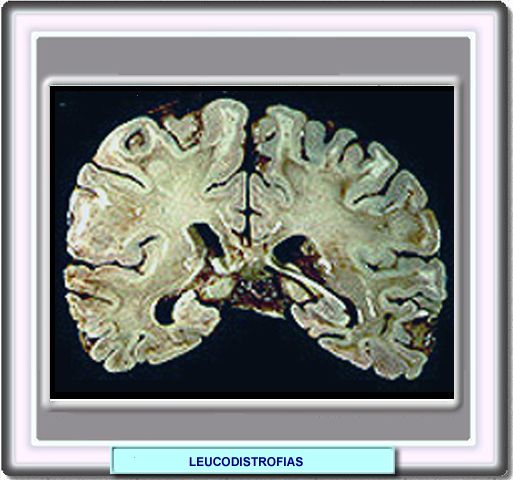

La pérdida de mielina del sistema nervioso central en las leucodistrofias puede ser masiva, usualmente bilateral. Ocasionalmente, puede verse afectada la mielina de los nervios periféricos, e incluso se encuentran lesiones distróficas fuera del sistema nervioso.

Normalmente, las leucodistrofias se manifiestan poco después del nacimiento, aunque existen formas de leucodistrofia de comienzo tardío.